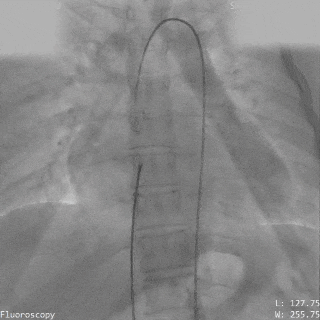

导丝通过主动脉窦瘤破口(左);导丝置于下腔静脉(右)